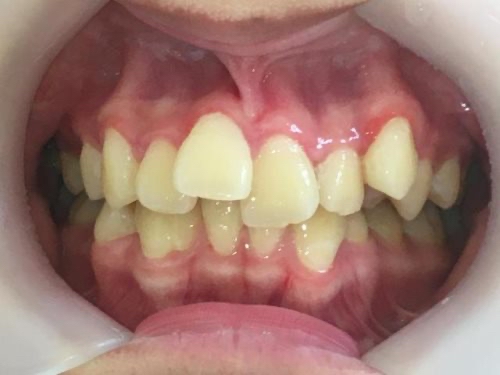

拝見したところ、歯並びの幅が狭くスペースが不足していることにより、全体的に歯が重なり合って並んでいる「叢生(そうせい)」でした。

また、上の歯並びが前方に出ている「上顎前突(じょうがくぜんとつ)」も見られ、唇が閉じにくく口呼吸が増えていました。

口呼吸で口の中が乾燥することにより細菌が増え、歯ぐきの炎症も起こっていました。